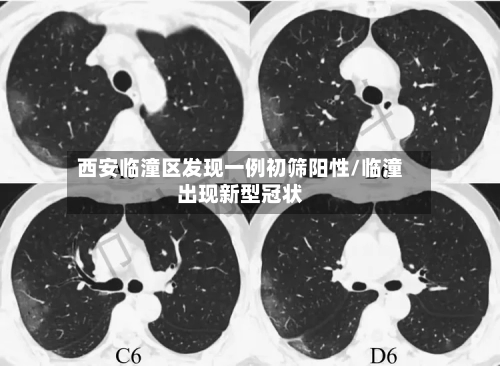

西安临潼区发现一例核酸初筛阳性人员,近来接触人员情况如何?

近来接触人员都已经按照规定报备,并且配合疫情防控的要求 ,接受隔离了。西安临潼区区发现一例核酸初筛阳性人员,近来已这名阳性人员有过间接性接触的人员基本上都已经按照当地的防疫规定向有关部门报备,并且配合相应的防疫措施 ,接受了隔离管控 。

月18日,西安市临潼区在集中隔离人员中发现一例无症状感染者。该病例曾于4月16日12:43至13:37在马额街道有活动轨迹,先后到马额街道旺盛达门业 、鸿运建材商店购买建材等。

临潼区紧急寻人 4月18日 ,西安市临潼区在集中隔离人员中发现一例无症状感染者。该病例曾于4月16日12:43至13:37在马额街道有活动轨迹,先后到马额街道旺盛达门业、鸿运建材商店购买建材等 。

〖壹〗 、临潼区紧急寻人 4月18日,西安市临潼区在集中隔离人员中发现一例无症状感染者 。该病例曾于4月16日12:43至13:37在马额街道有活动轨迹,先后到马额街道旺盛达门业、鸿运建材商店购买建材等。请4月16日以来去过马额街道的人员 ,立即就近向所在村委会(社区)或疫情防控部门进行报备,并落实从4月16日到21日5天3次核酸检测要求。